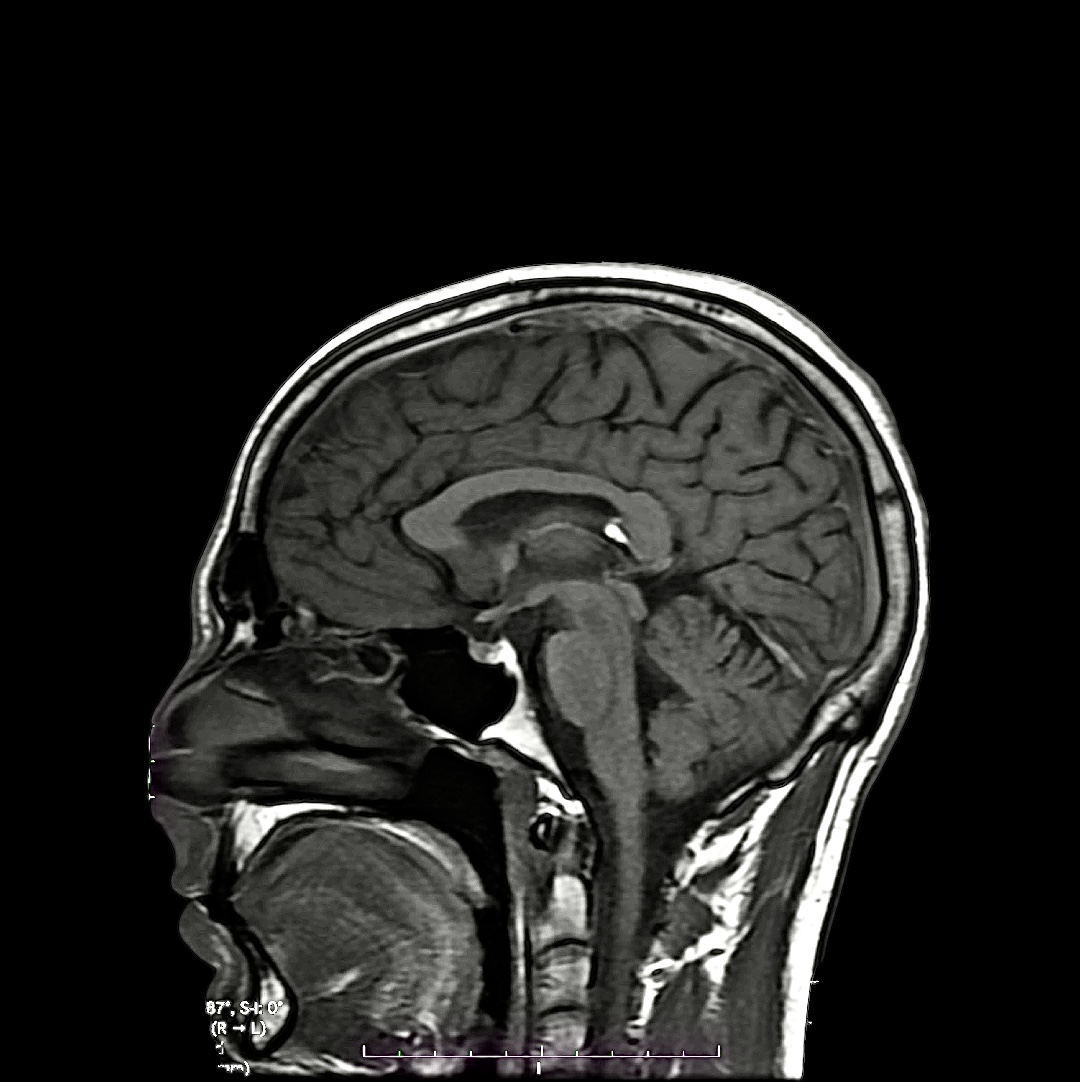

Neuromelanin-sensitive MRI

My brain — Pittsburgh, PA